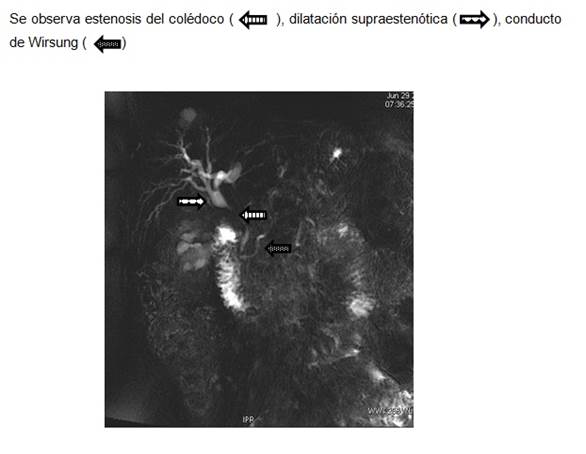

Mujer de 62 años, con antecedentes personales de hipotiroidismo, sin antecedentes de cirugía abdominal, con diagnóstico de síndrome de intestino irritable (episodios repetidos de dolor abdominal, sin síntomas atribuibles a la esfera hepatobiliar, con laboratorio, ecografía y endoscopias digestivas (alta y baja) normales). Consultó por un nuevo episodio de dolor abdominal de características clínicas similares pero con una bioquímica que mostraba una bilirrubina total de 0,62 mg/dl, fosfatasa alcalina de 509 U/l (20-240), gama-glutamil-transpeptidasa de 221 U/l (5-36), aspartato-transferasa de 95 U/l (5-27), alanino-transferasa de 125 U/l (5-33), con proteínas totales 7,30 g/dl, albúmina 4 g/dl, tasa de protrombina 72%, hemoglobina 12,1 g/dl (12,0-15,5), glóbulos blancos 7.9 mil/mm3 (4,3-10), plaquetas 331 mil/mm3 (130-440). La ecografía de abdomen (Figura 1a) mostró un hígado de forma y tamaño habitual, sin alteración de la ecogenicidad, de bordes regulares y sin lesiones focales. La vía biliar intrahepática presentaba leve dilatación y el colédoco proximal medía 9 mm. La vesícula biliar presentaba paredes engrosadas y se encontraba poco distendida a pesar del ayuno. El bazo medía 150 mm de longitud. En el estudio doppler (Figura 1b) no se identificó vena porta permeable, el hilio hepático presentaba varias estructuras vasculares algunas trombosadas, otras con calibre fino que correspondían a la transformación cavernomatosa de la vena porta. Las ramas portales intrahepáticas se encontraban permeables. La arteria hepática estaba aumentada de calibre y tortuosa al igual que sus ramas intrahepáticas. La colangioresonancia magnética mostró (Figura 2): estenosis de tercio medio de colédoco de una longitud aproximada de 2,5 cm, de bordes regulares, con dilatación proximal del colédoco, hilio y vía biliar intrahepática. No se observaba el cístico ni la vesícula biliar. El Wirsung no presentaba alteraciones. La videogastroscopía (VGC) informaba várices esofágicas grandes con puntos rojos que se extendían hacia el cardias y fondo gástrico (GOV-2). Las dosificaciones de CA 19-9 e IgG4 fueron 10,0 U/l (0,0-35) y 291 mg/dl (3,0-201), respectivamente. En la Tabla 1 se detallan los resultados de los estudios de la coagulación. La citometría de flujo en sangre periférica para el diagnóstico de hemoglobinuria paroxística nocturna no constató déficit de glucosil fosfatidil-inositol en las células sanguíneas (monocitos, eritrocitos, granulocitos).